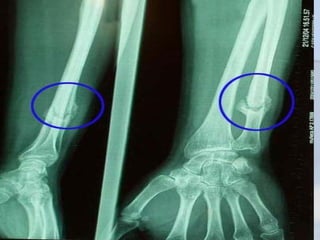

   Radiológicamente se observa la línea

   RX: descalcificación delos extremos

PSEUDOARTROSIS

la ostogénesis y radiográficamente se

DIAGNOSTICO

   RX: se observa recalsicacion y